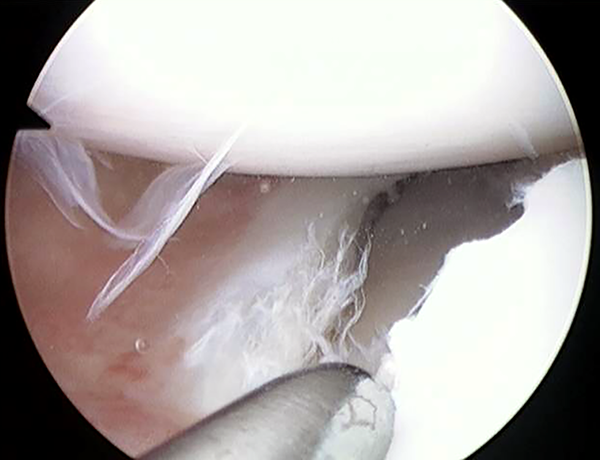

Figura 5:

Al retirar las agujas se recuperan las suturas fuera de la articulación, se realiza un nudo deslizante desde afuera y se lo introduce a través del tejido subcutáneo mediante una pequeña incisión en la piel, para finalmente atarlo sobre la capsula articular.

Figura 6:

Vision artroscópica intraarticular luego del tensado de los puntos fuera dentro.